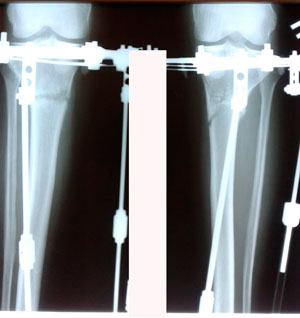

Исходник - 48 лет.

Диагноз: варусная формация голеней.

Дата операции - 17.10.2019г.

на фиксации